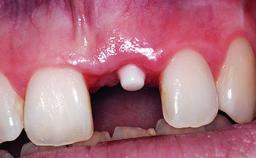

A 32-year-old female Caucasian patient with a compromised maxillary right central incisor was referred to us by a general dentist. Her chief complaints were discomfort and mobility of tooth 11 with unsatisfactory esthetics due to discoloration. The patient reported a previous trauma, some years earlier, as the origin of pathology on the afflicted tooth. Anamnesis was negative for any other dental or periodontal pathology in the remaining dentition. The patient did not take any medication and reported to be a light smoker (5–10 cigs/day). She had high esthetic expectations of her treatment. The extraoral examination revealed a high smile line with full exposure of her maxillary teeth and surrounding soft tissue in the area between the second premolars.

Placement Protocol Early or late implant placement

Bone Volume Deficient horizontally, requiring prior grafting

Esthetic Risk High